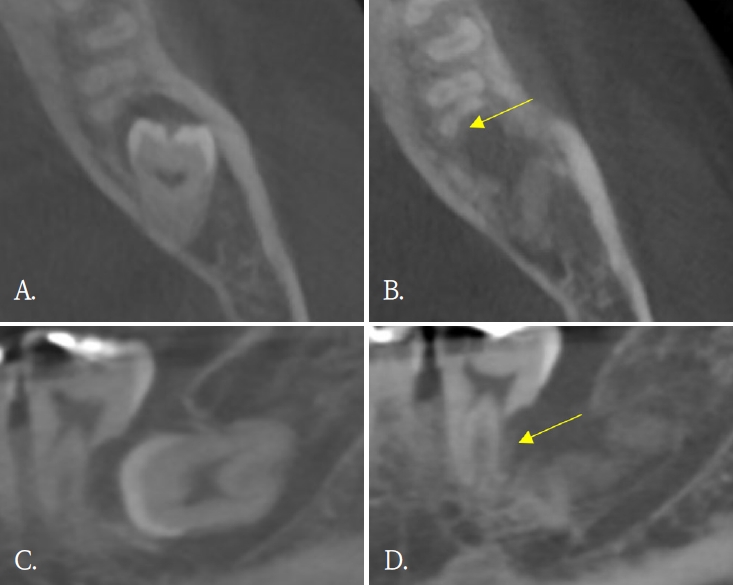

In 6 of 10 patients, dentin bridge formation and bone healing at the PRF application site were visible on panoramic radiographs (Figs. 1 and 2), excluding 4 patients who returned only once within one month postoperatively. In Table 2, patients who presented radiographic improvement and patients who had uncertain radiographic results due to insufficient follow-up period were described. In addition to bony healing, dental pulp atrophy was detected in a case (Fig. 3). No additional ERR was observed in any patients. Only one patient had preoperative and postoperative CBCT, and dentin formation and bony healing was seen on CBCT 6 months after surgery.

Dentin formation (yellow arrows). A and C. Pre-operative cone-beam computed tomographic (CBCT) images. B and D. Post-operative CBCT after 6 months of surgery.